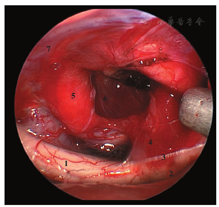

神经垂体与垂体柄延续,且二者与腺垂体之间存在软膜结构。在肿瘤生长过程中,神经垂体和垂体柄表面这层软膜结构一直存在,因此,肿瘤与神经垂体和垂体柄之间往往存在可辨认的界面[10](图5)。